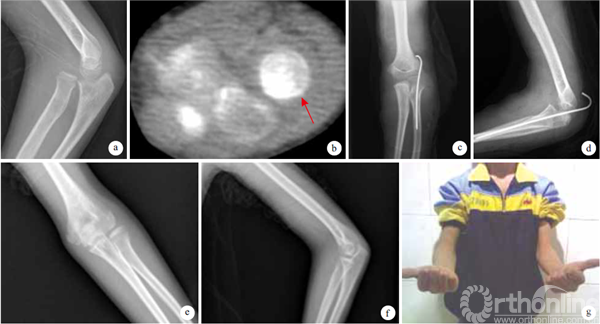

术后切口均期愈合,无感染、关节僵硬、桡骨头坏死等并发症发生。1例单纯陈旧性桡骨小头脱位患儿于术后2.5个月发生再脱位,未接受进一步处理并失访;24例获随访,随访时间2958个月,平均44.3个月。获随访的24例患儿桡骨小头均复位,其中2例陈旧性孟氏骨折患儿,术后6个月尺骨截骨处达骨性愈合并取出钢板。3例合并桡神经损伤患儿,其中2(包括陈旧性孟氏骨折1)神经功能完全恢复;1例桡神经损伤达9个月者神经功能无明显改善,仍不能伸腕及伸拇,但肘关节屈伸及前臂旋转功能恢复正常。除1例桡神经损伤患儿功能无明显改善外,余23例患儿术后均无关节疼痛、畸形及活动受限;活动范围:肘关节屈曲125140°,平均134°;伸直—8,平均—4°;前臂旋前6580°,平均74°;旋后均达90°。术后2年,按照Mackay等功能评价标准,获优22例,良1例,差1例,优良率达95.8%。 见图1